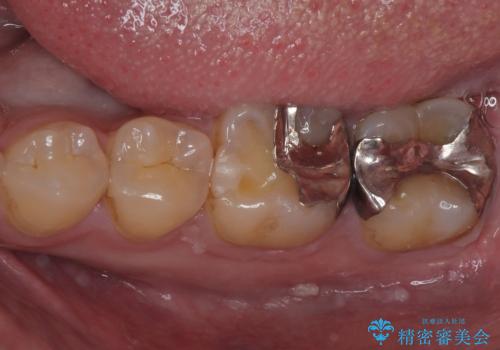

銀歯の下の虫歯を治したい オールセラミッククラウン・セラミックインレー修復